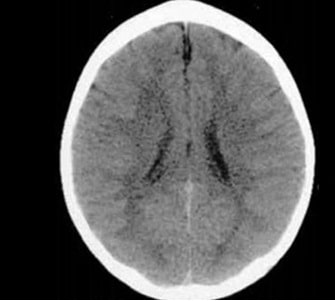

Duas tomografias divulgadas pelo Texas Children’s Hospital, nos Estados Unidos evidenciaram o impacto que o amor dos pais causa na vida dos filhos. Essa primeira imagem é de uma criança de três anos que sempre ganhou muito carinho e atenção dos pais desde que nasceu: